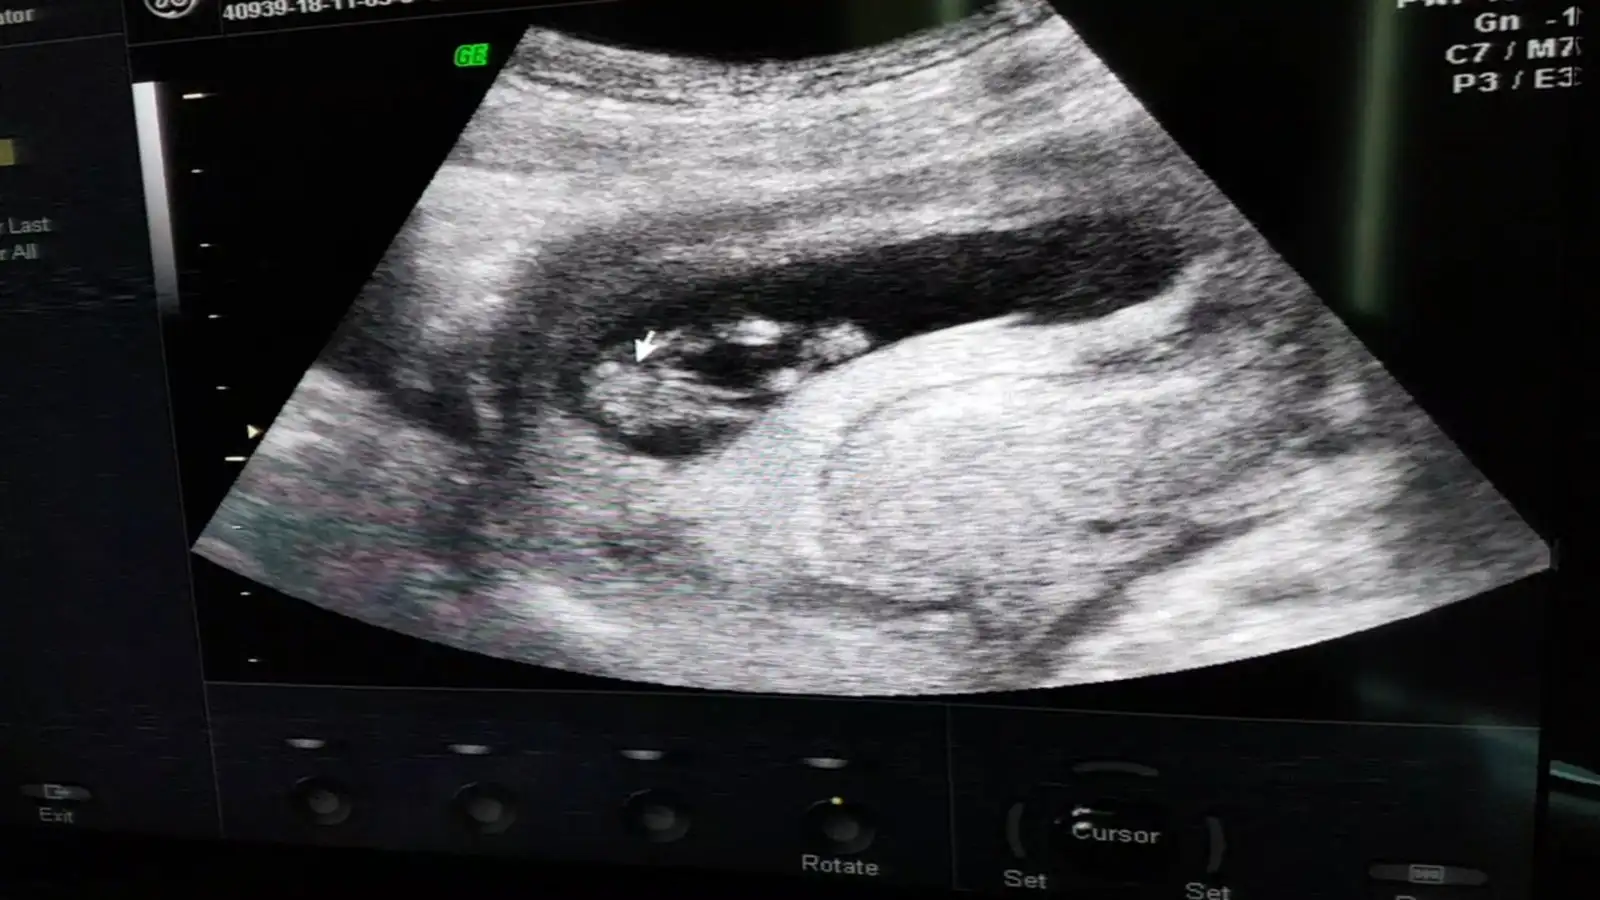

pipi gibi bişey nasıl acaba buna benziyor muydu

Eklentiler

• Screenshot_20181105-111609_Video Player.webp

Screenshot_20181105-111609_Video Player.webp

56,7 KB · Görüntüleme: 84